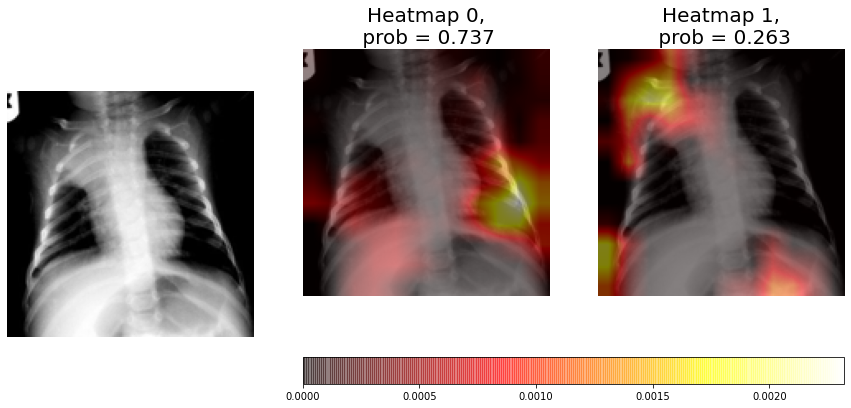

Figure 6 shows the prediction and heatmaps of an individual CNN for a non-consolidation test sample. The non-consolidation probability estimated by the model is 99.9%. If we analyse and compare the heatmaps, we can see that neuron 0 heatmap (non-consolidation) is clearly brighter than neuron 1 heatmap (consolidation), and in neuron 1 heatmaps there are different areas marked that shouldn’t be, corresponding to the clavicle and diaphragm. The conclusion is that the CNN has not found any signs of consolidation, but the previously referred areas of neuron 1 heatmap should not be lighted up.

In Figure 8 we can see in neuron 1 heatmap that there is a consolidation sign in the upper left lung, but the consolidation probability estimated by the model is only 26.3%. The conclusions is that the CNN model incorrectly classified the X-ray as a non-consolidation sample but the heatmap is able to find the consolidation evidences.